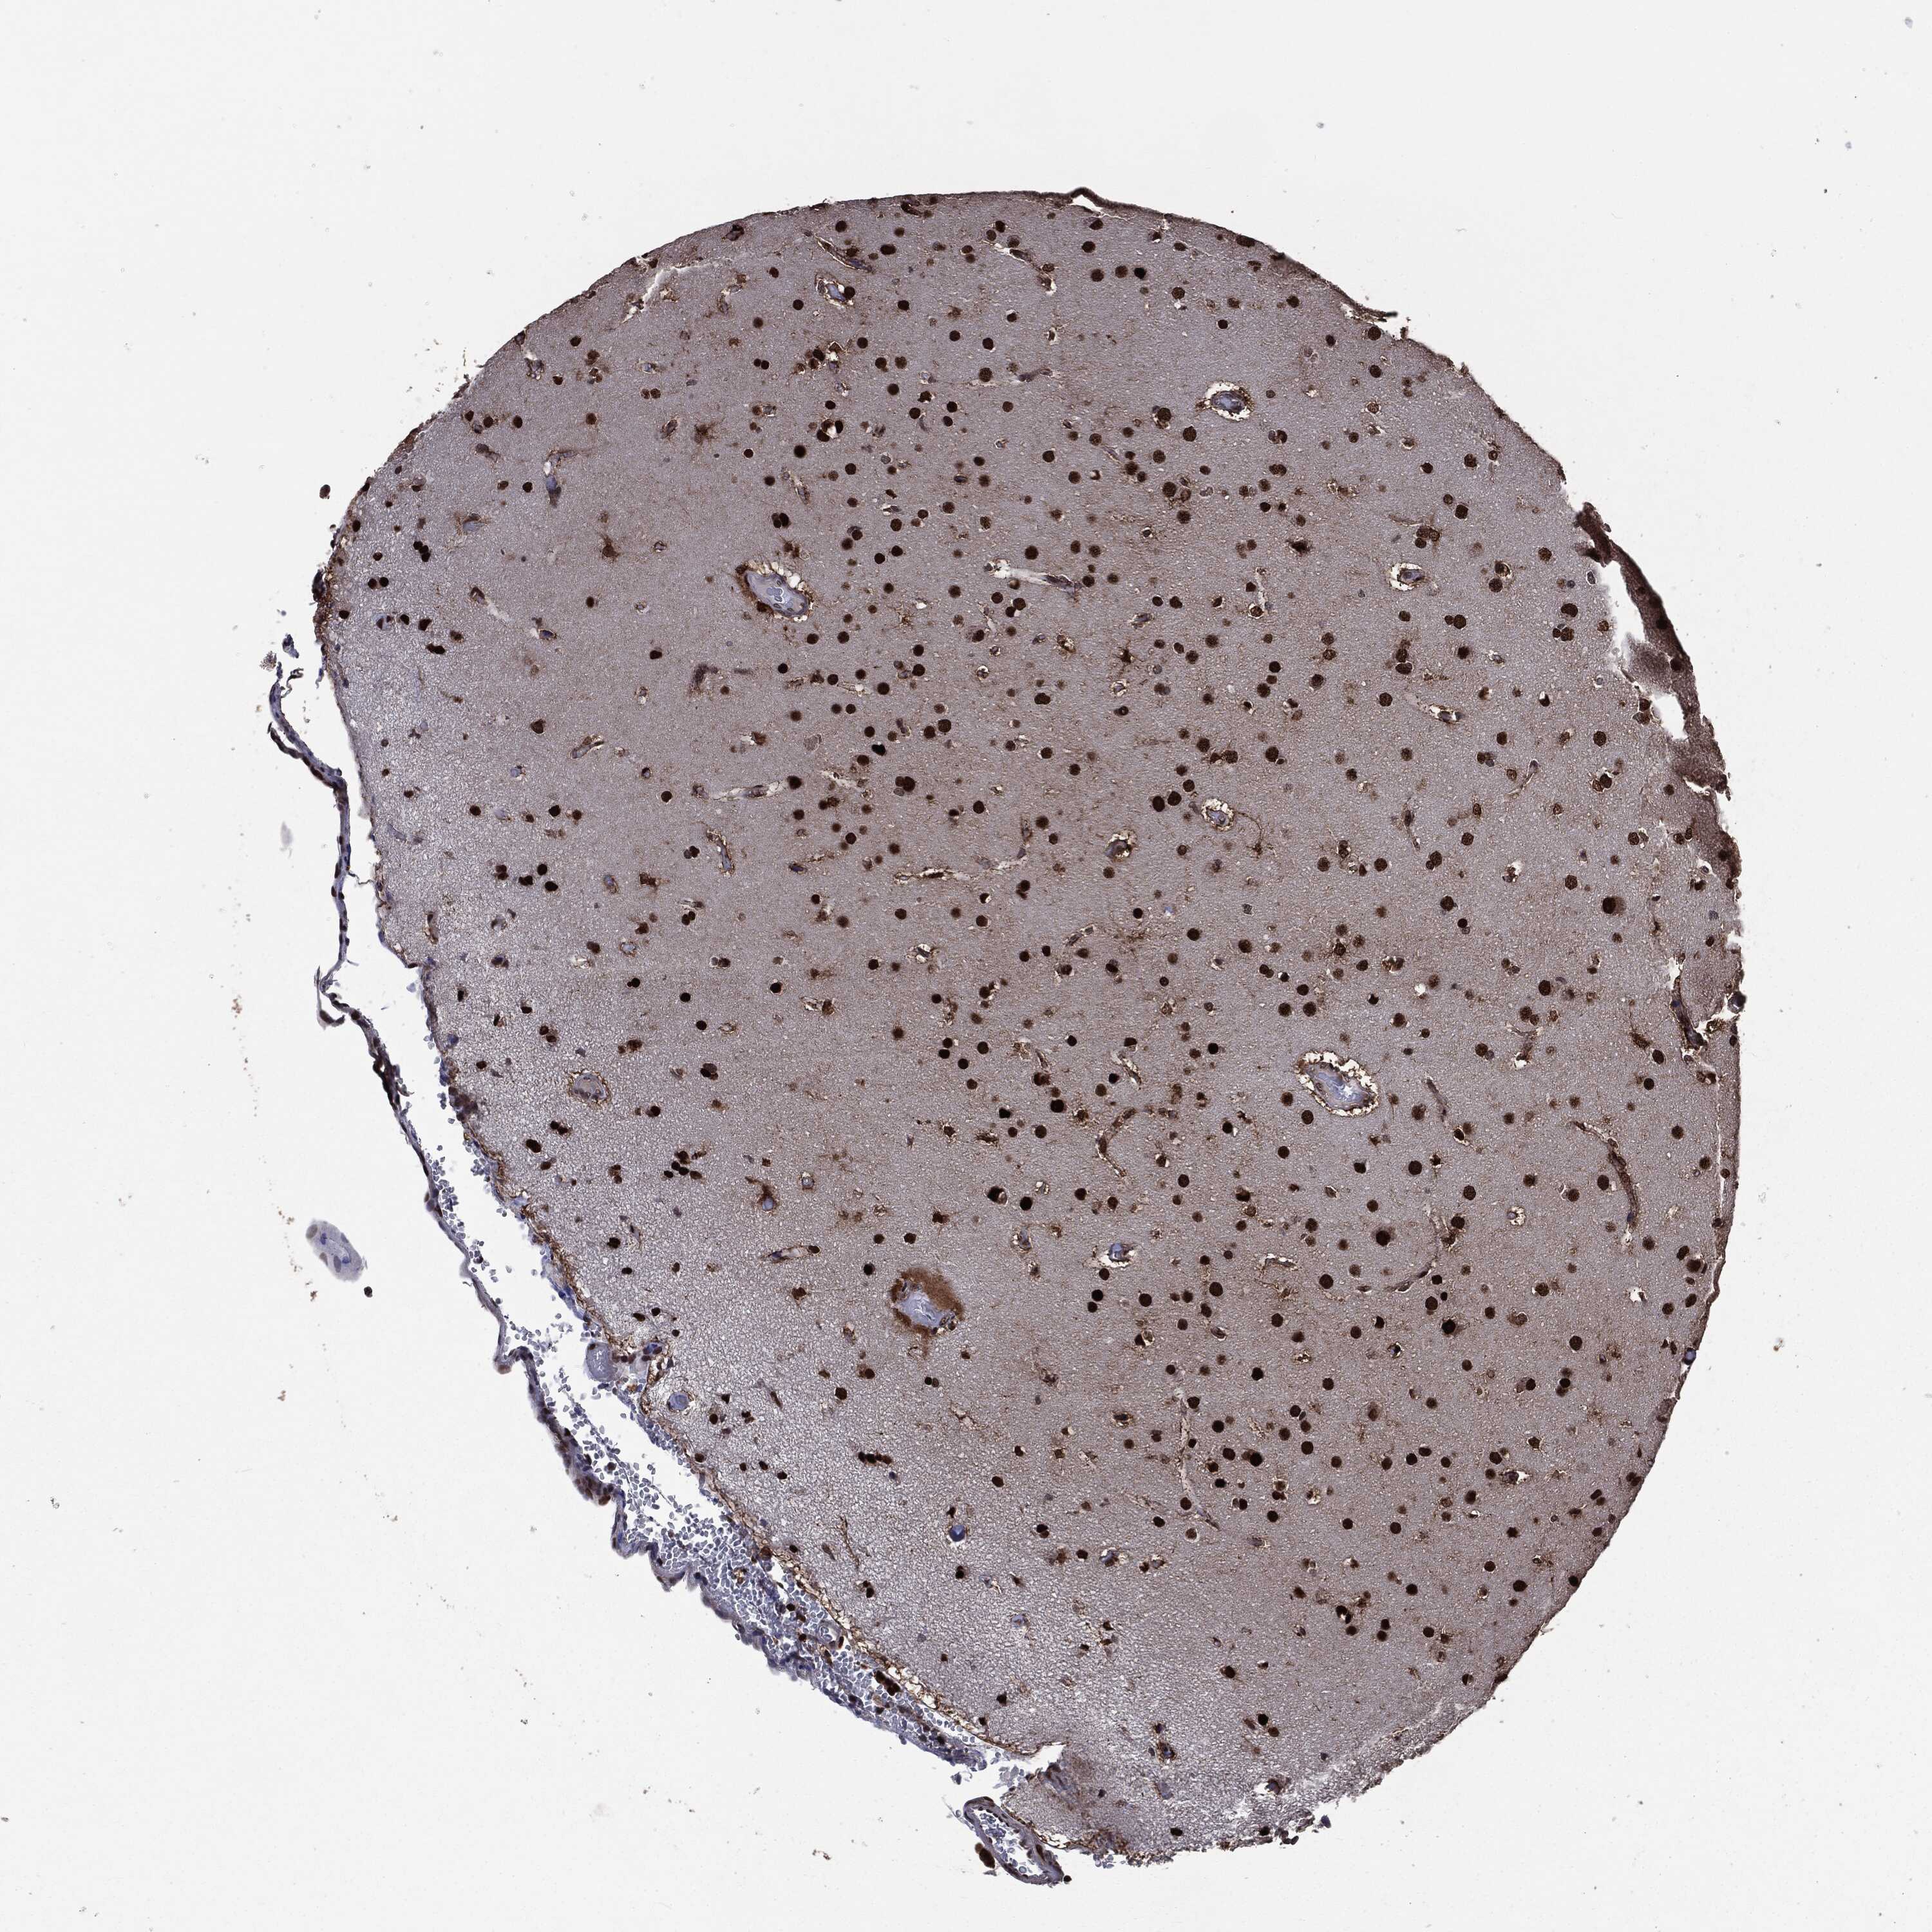

GLIOMA - Protein expressioni

A mouse-over function shows sample information and annotation data. Click on an image to view it in a full screen mode. Samples can be filtered based on level of antibody staining by selecting one or several of the following categories: high, medium, low and not detected. The assay and annotation is described here.

Note that samples used for immunohistochemistry by the Human Protein Atlas do not correspond to samples in the TCGA dataset.

Antibody stainingi

Antibody staining in the annotated cell types in the current human tissue is reported as not detected, low, medium, or high, based on conventional immunohistochemistry profiling in selected tissues. This score is based on the combination of the staining intensity and fraction of stained cells.

Each image is clickable and will lead to virtual microscopy that enables deeper exploration of all samples and also displays staining intensity scores, fraction scores and subcellular localization as well as patient and tissue information for each sample.

Antibody HPA022914

Antibody HPA064732

Staining

High

Medium

Low

Not detected

Intensity

Strong

Moderate

Weak

Negative

Quantity

>75%

75%-25%

<25%

None

Location

Nuclear

Cytoplasmic/membranous

Cytoplasmic/membranous,nuclear

Glioma, malignant, High grade

Glioma, malignant, Low grade

Glioma, malignant, NOS